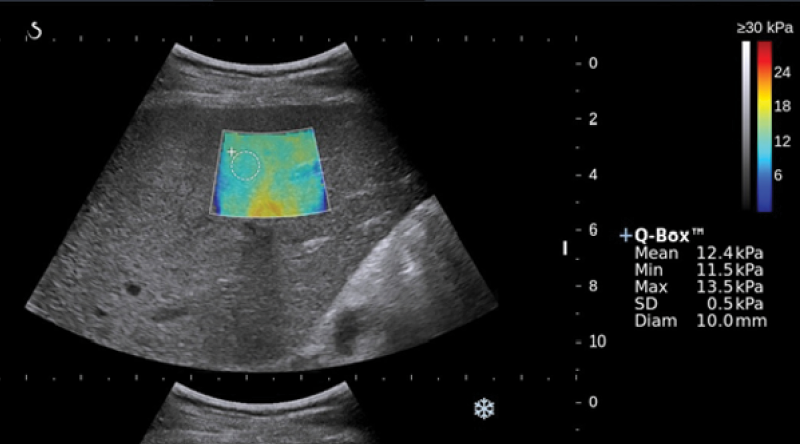

Messung der Lebersteifigkeit und -verfettung mittels transienter Elastographie mit CAP-Wert FibroScan ® und Shearwave-Elastographie

Die Erfassung der Lebersteifigkeit ist ein etablierter Bestandteil in der Diagnostik und der Einschätzung des Schweregrades der Leberfibrose, Feststellung der Leberzirrhose und der Erfassung der portalen Hypertension. Neben der Ultraschalldiagnostik können wir mittels des CAP-Wertes die Verfettung der Leber einschätzen. Besonderer Vorteil besteht in dem nicht-invasiven Charakter dieser Untersuchungen, d.h. eine Biopsie ist nicht mehr erforderlich und es bestehen keine Risiken.